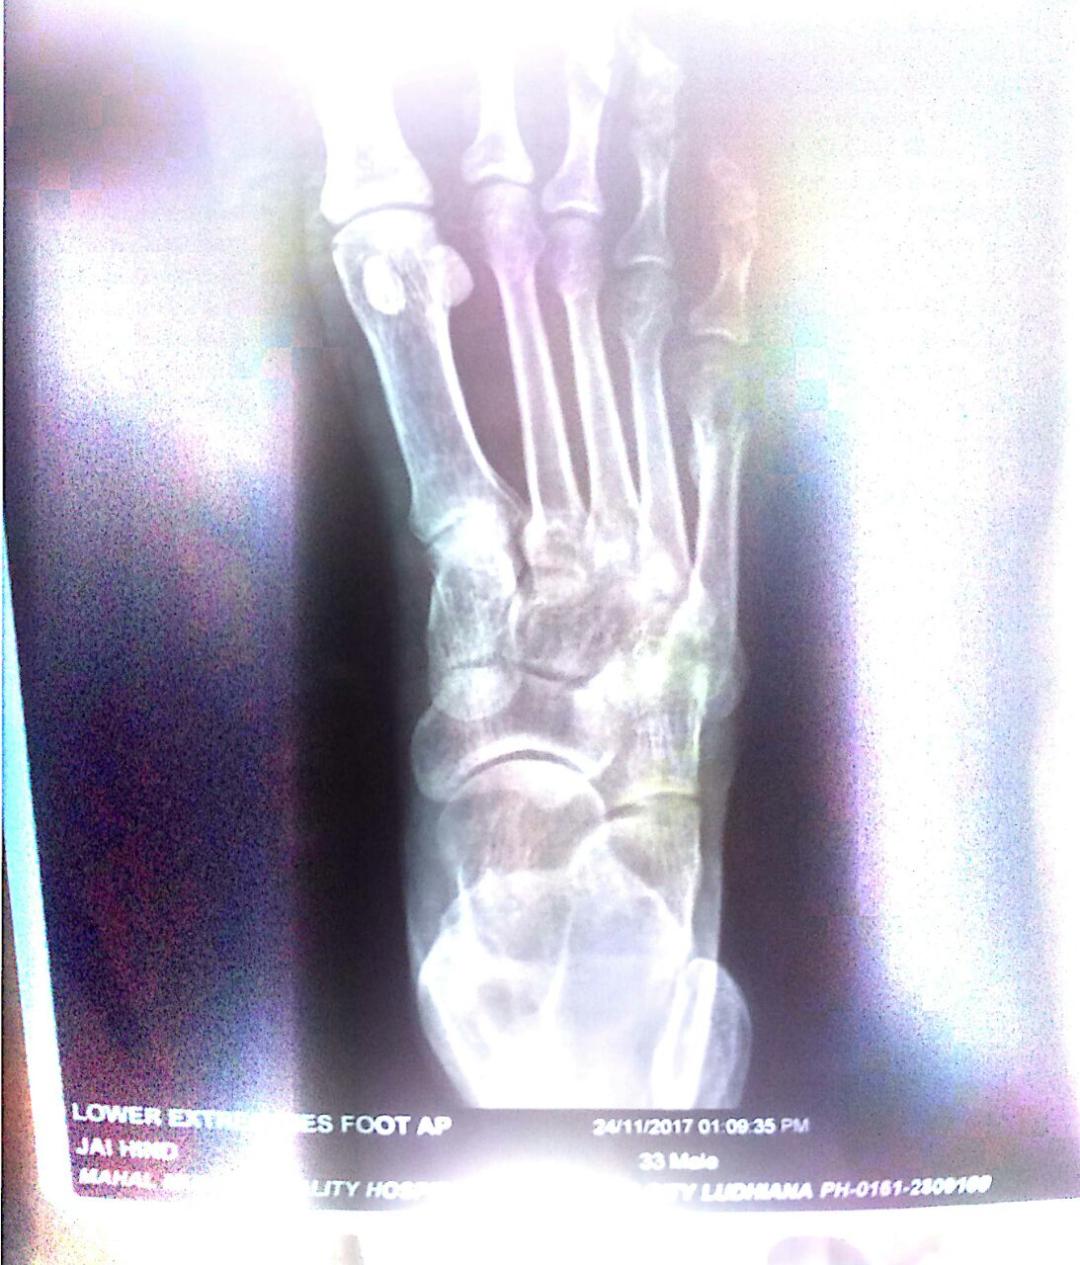

Doctors Made False Reports Dt. 20-08-2017